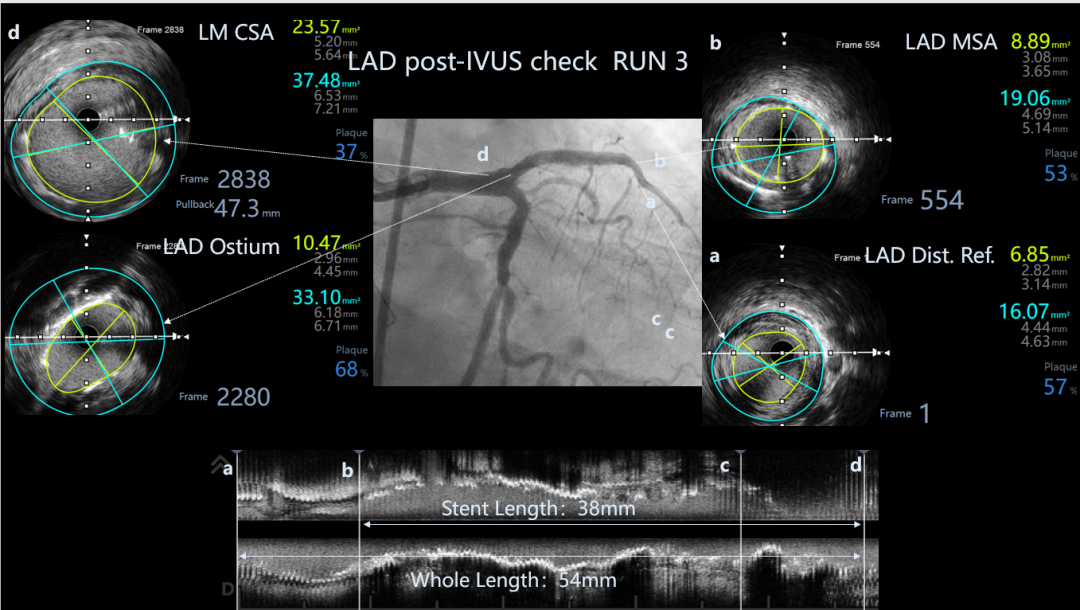

LAD post-IVUS check RUN 3

Ballon 2.5*15mm, 3.0*15mm Dilatation & IVUS check

LAD Stent Synergy 3.5*38mm

Ballon QM 4.0*12mm, 5.0*8mm Dilatation & POT